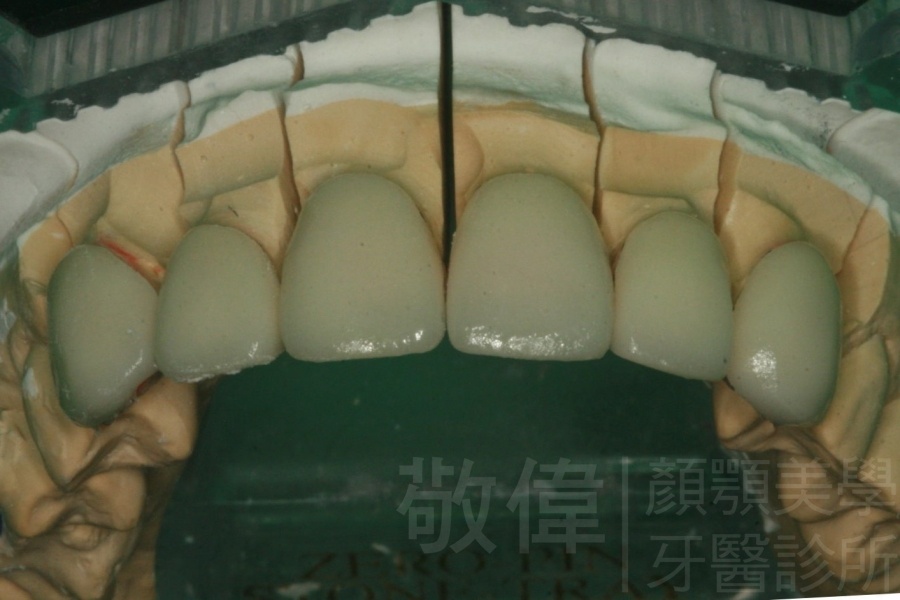

| 6 | 前牙美容 | 矯正+牙齦增補+晶鑽全瓷冠 | ||

| 7 | 前牙美容 | 矯正+晶鑽全瓷冠 | ||